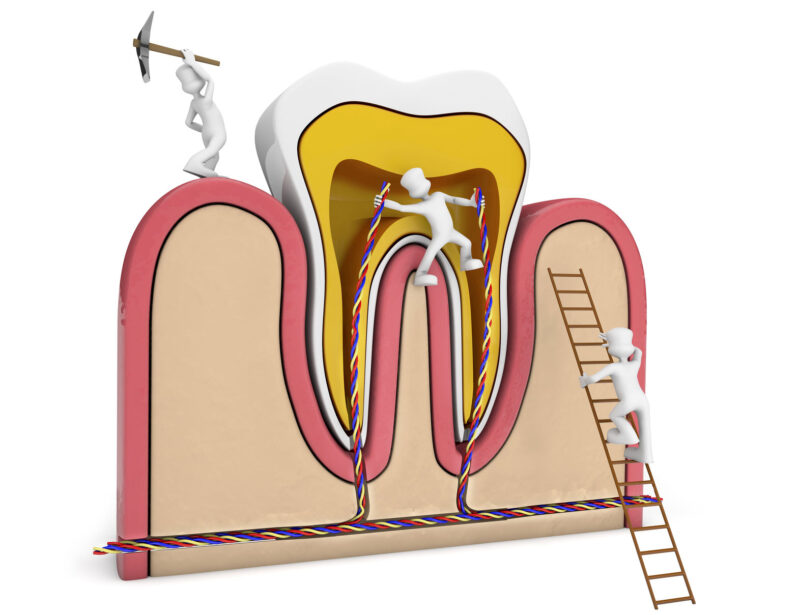

درمان ریشه:

وقتی پوسیدگی دندان شدید باشد، ممکن است به مغز دندان سرایت کند در این حال ، با رسیدن پوسیدگی به عصب دندان ، درد شدید بروز می یابد. در اندو یا همان عصب کشی ، لازم است این عصب اصطلاحا ازبین برود.